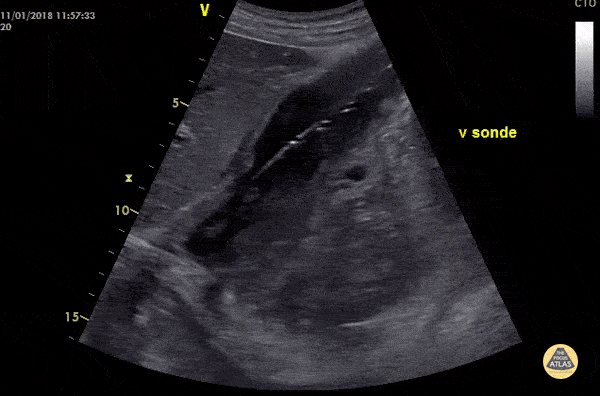

Control of gastric feeding tube. Case of gastric tube placed in the stomach. You might consider the use of color doppler to see flow pattern in the lumen. Dr. Birkelund